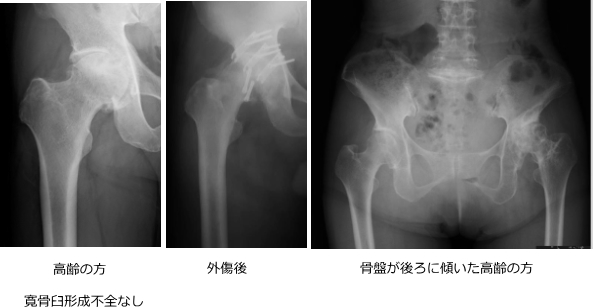

1.寛骨臼形成不全

股関節の受け皿が浅く、大腿骨頭を十分に覆えていない状態です。

日本人女性に多く、変形性股関節症の約9割がこれに関連しています。

この状態では、関節の一部に負担が集中し、軟骨の摩耗が進行します。

高齢になると、姿勢の変化(骨盤後傾など)によっても関節への負担が増します。